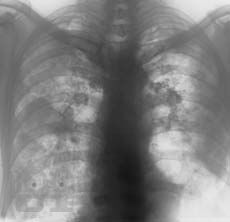

Клинико-рентгенологическая диагностика болезней органов дыхания

Основу данной книги составил архив клинико-рентгенологических наблюдений, собранный авторами в течение ряда лет. Авторы не стремились к подробному описанию клинико-рентгенологической диагностики многочисленных заболеваний бронхолёгочной системы. Материал излагается кратко, почти тезисно и отражает наиболее важные сведения об основной патологии органов дыхания. Цель книги — отражение вопросов клинической картины и рентгенодиагностики распространённых бронхолёгочных заболеваний в условиях муниципальных учреждений здравоохранения с позиции врача общей практики. Предназначено для терапевтов, семейных врачей, студентов медицинских вузов.